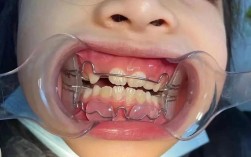

方案确定后,进入牙箍佩戴阶段,传统矫正需在牙齿表面粘接托槽(金属托槽为银色,陶瓷托槽为透明,更美观),再将弓丝嵌入托槽,通过结扎丝或橡皮圈固定;自锁托槽则带有闭锁装置,弓丝可直接嵌入,减少摩擦力,可能缩短矫正时间;隐形矫正通过一系列透明牙套套住牙齿,每副牙套佩戴1-2周,更换下一副时牙齿会轻微移动。